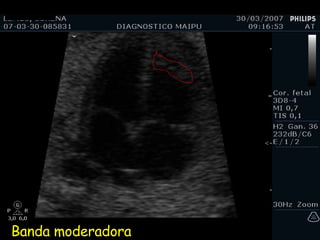

EXAMEN BASICO VENTRICULOS Tamaños Paredes Banda moderadora Tabique

Banda moderadora